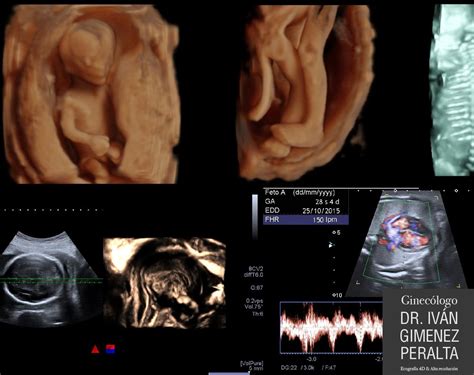

El bebé mide entre 11 y 13 centímetros y pesa alrededor de 100 a 140 gramos. Sus movimientos se vuelven más enérgicos y frecuentes, aunque es posible que aún no los percibas. Los ojos y los oídos evolucionan, los ojos están cerrados pero ya son sensibles a la luz, y las orejas se acercan a su posición final.

El esqueleto cartilaginoso del bebé comienza a endurecerse, transformándose gradualmente en hueso. Sus latidos cardíacos son lo suficientemente fuertes como para ser escuchados con un estetoscopio o un doppler. El cuerpo del bebé empieza a ser más grande que su cabeza, y un fino vello cubre su cráneo.

En la semana 17, el feto ya acumula tejido adiposo, esencial para mantener su calor corporal. La vérnix caseosa, una sustancia grasa blanquecina que protege su piel, comienza a aparecer. Si se realiza una ecografía, es posible que ya se pueda determinar el sexo del bebé.

La segunda ecografía, realizada alrededor de la semana 20, es crucial para evaluar el desarrollo de los órganos del bebé y detectar posibles anomalías. En esta ecografía, si lo deseas, se puede conocer el sexo del bebé con mayor seguridad.